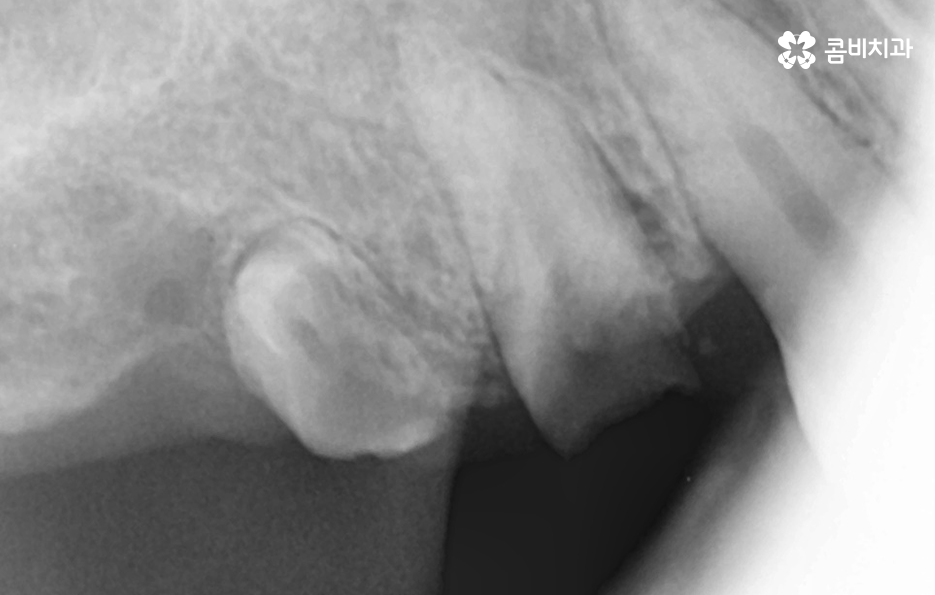

우선 임플란트 치료에 있어서 뼈이식이 필요한 이유에 대해 이해하시면 좋은데 임플란트의 치료 과정에서 뼈이식을 추가적으로 진행하는 이유에는 임플란트를 식립할 잇몸 뼈의 충분한 두께와 깊이가 확보되지 않을 때 임플란트를 안정적으로 식립하기 위해 뼈이식이 진행되고 있는데요

뼈이식은 뼈가루를 말랑하게 점토처럼 반죽하여 잇몸 안에 이식을 하고 단단하게 기존의 뼈처럼 굳기 까지 평균적으로 약 2~4개월 정도가 걸리는데 환자분의 건강 상태에 따라서는 6개월 이상도 걸릴 수 있어요